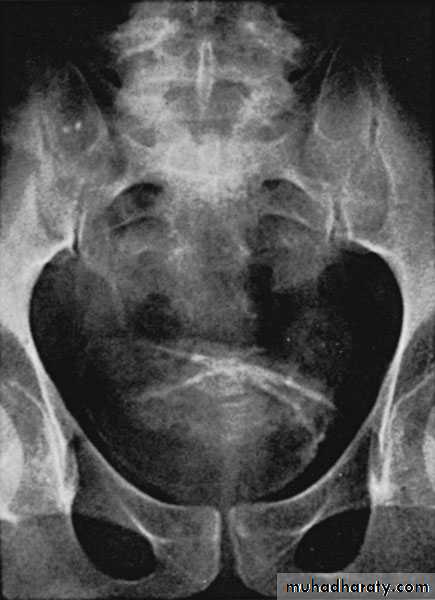

KUB: Renal calcification

KUB

IVU